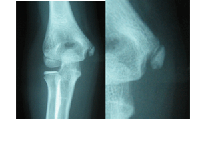

外側型 上腕骨小頭離断性骨軟骨炎

上腕骨外側(親指側)の痛みです

レントゲンでは上腕骨小頭に透亮像

が現れます。進行すると軟骨が分離

して遊離体を形成します。